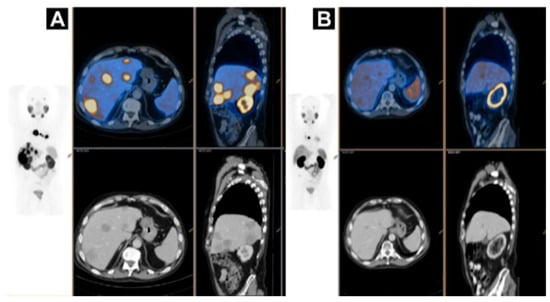

SPECT and PET imaging using anti-HER2 Affibody® molecule [177,178,179,180,181,182] demonstrated the potential of safe, whole-body, and non-invasive “biopsy”, allowing receptor expression heterogeneity profiling (Figure 11), in clinical trials with ongoing multicenter Phase II/III one (NCT03655353) [5,183,184,185,186,187]. [68Ga]Ga-ABY-025 PET-CT presents advantages over [111In]In-ABY-025/SPECT/CT in terms of simpler logistics, higher resolution, higher detection rate, dynamic scanning, and accurate quantification [5,183] potentially allowing staging, prognosis, patient selection, quantification of the receptor expression and therapeutic drug dose estimation, early monitoring of the treatment response and resistance, residual disease, follow-up, and relapse.

Figure 11.

Based on the results from [68Ga]Ga-ABY-025 PET/CT, mixed expression of HER2 in metastatic breast cancer was seen in several patients and confirmed by biopsies in two. Patient 9 had HER2-negative primary tumor and was enrolled as negative control. [18F]FDG-PET/CT showed metastases in left liver lobe, peritoneal lymph nodes, and cervix of uterus. [68Ga]Ga-ABY-025 uptake was high in the liver metastasis, low in peritoneal metastases and absent in the cervical region (not shown). According to IHC, the liver finding was true positive and both other sites were true negative. Adopted from [5].